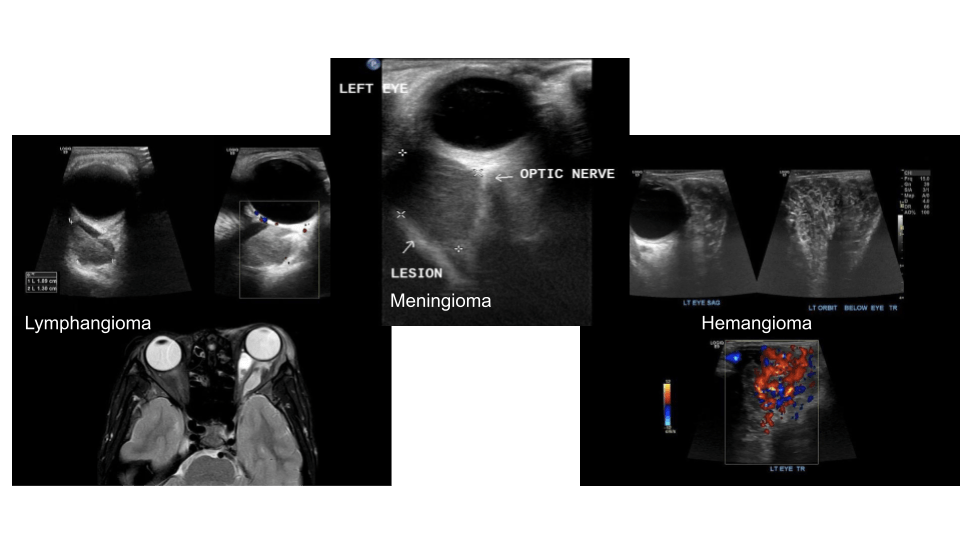

Retro Orbital

Retorbital masses may be of hematogenous (i.e. from trauma) or lesions (benign/malignant)

Sonographically you’ll want to increase the depth to appreciate the posterior structures.